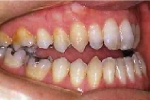

| 初診時

|